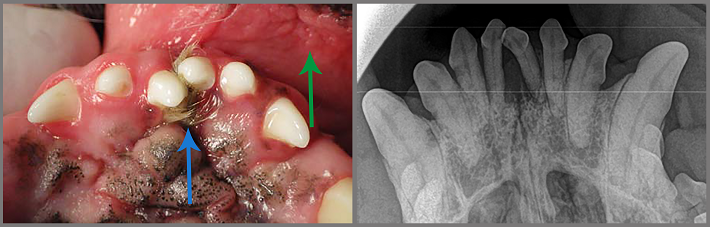

De volgende foto laat een ontstoken binnenkant van de lippen zien (groene pijl). De snijtanden staan zo afwijkend dat er haar en vuil tussen vastzit (blauwe pijl). Op de bijbehorende röntgenfoto is te zien dat de twee middelste snijtanden los staan, het bot is daar verdwenen door botontsteking.